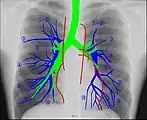

Radioanatomy (x-ray anatomy) is anatomy discipline which involves the study of anatomy through the use of radiographic films.[1] The x-ray film represents two-dimensional image of a three-dimensional object due to the summary projection of different anatomical structures onto a planar surface.

It requires certain skills for the correct interpretation of such images. Radiological anatomy is a necessary component of training for radiologists as well as medical students.